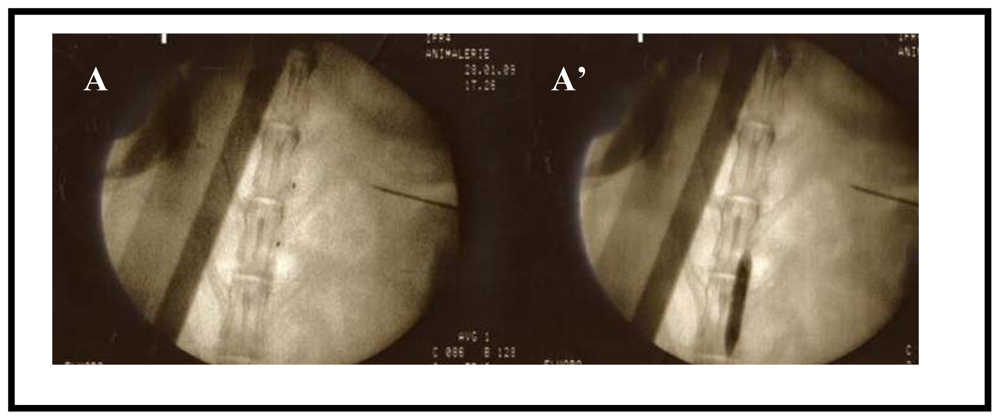

2.1. Rabbit model of Atherosclerosis

2.2. In Vivo Biopanning

3.1. Animal Model

3.2. Magnetic Resonance Imaging

3.5. Sequencing of Randomly Picked Clones